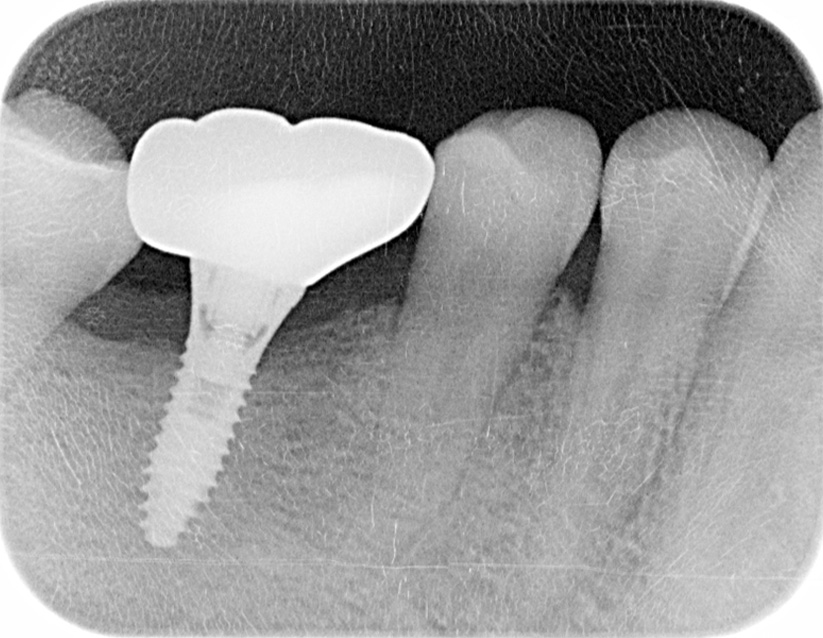

インプラント手術から3ヵ月後、型どりをして、仮歯を製作しました。

レントゲン画像 -

仮歯の調整期間を経て、セラミックの歯が入りました。

レントゲン画像 治療前 インプラント治療後